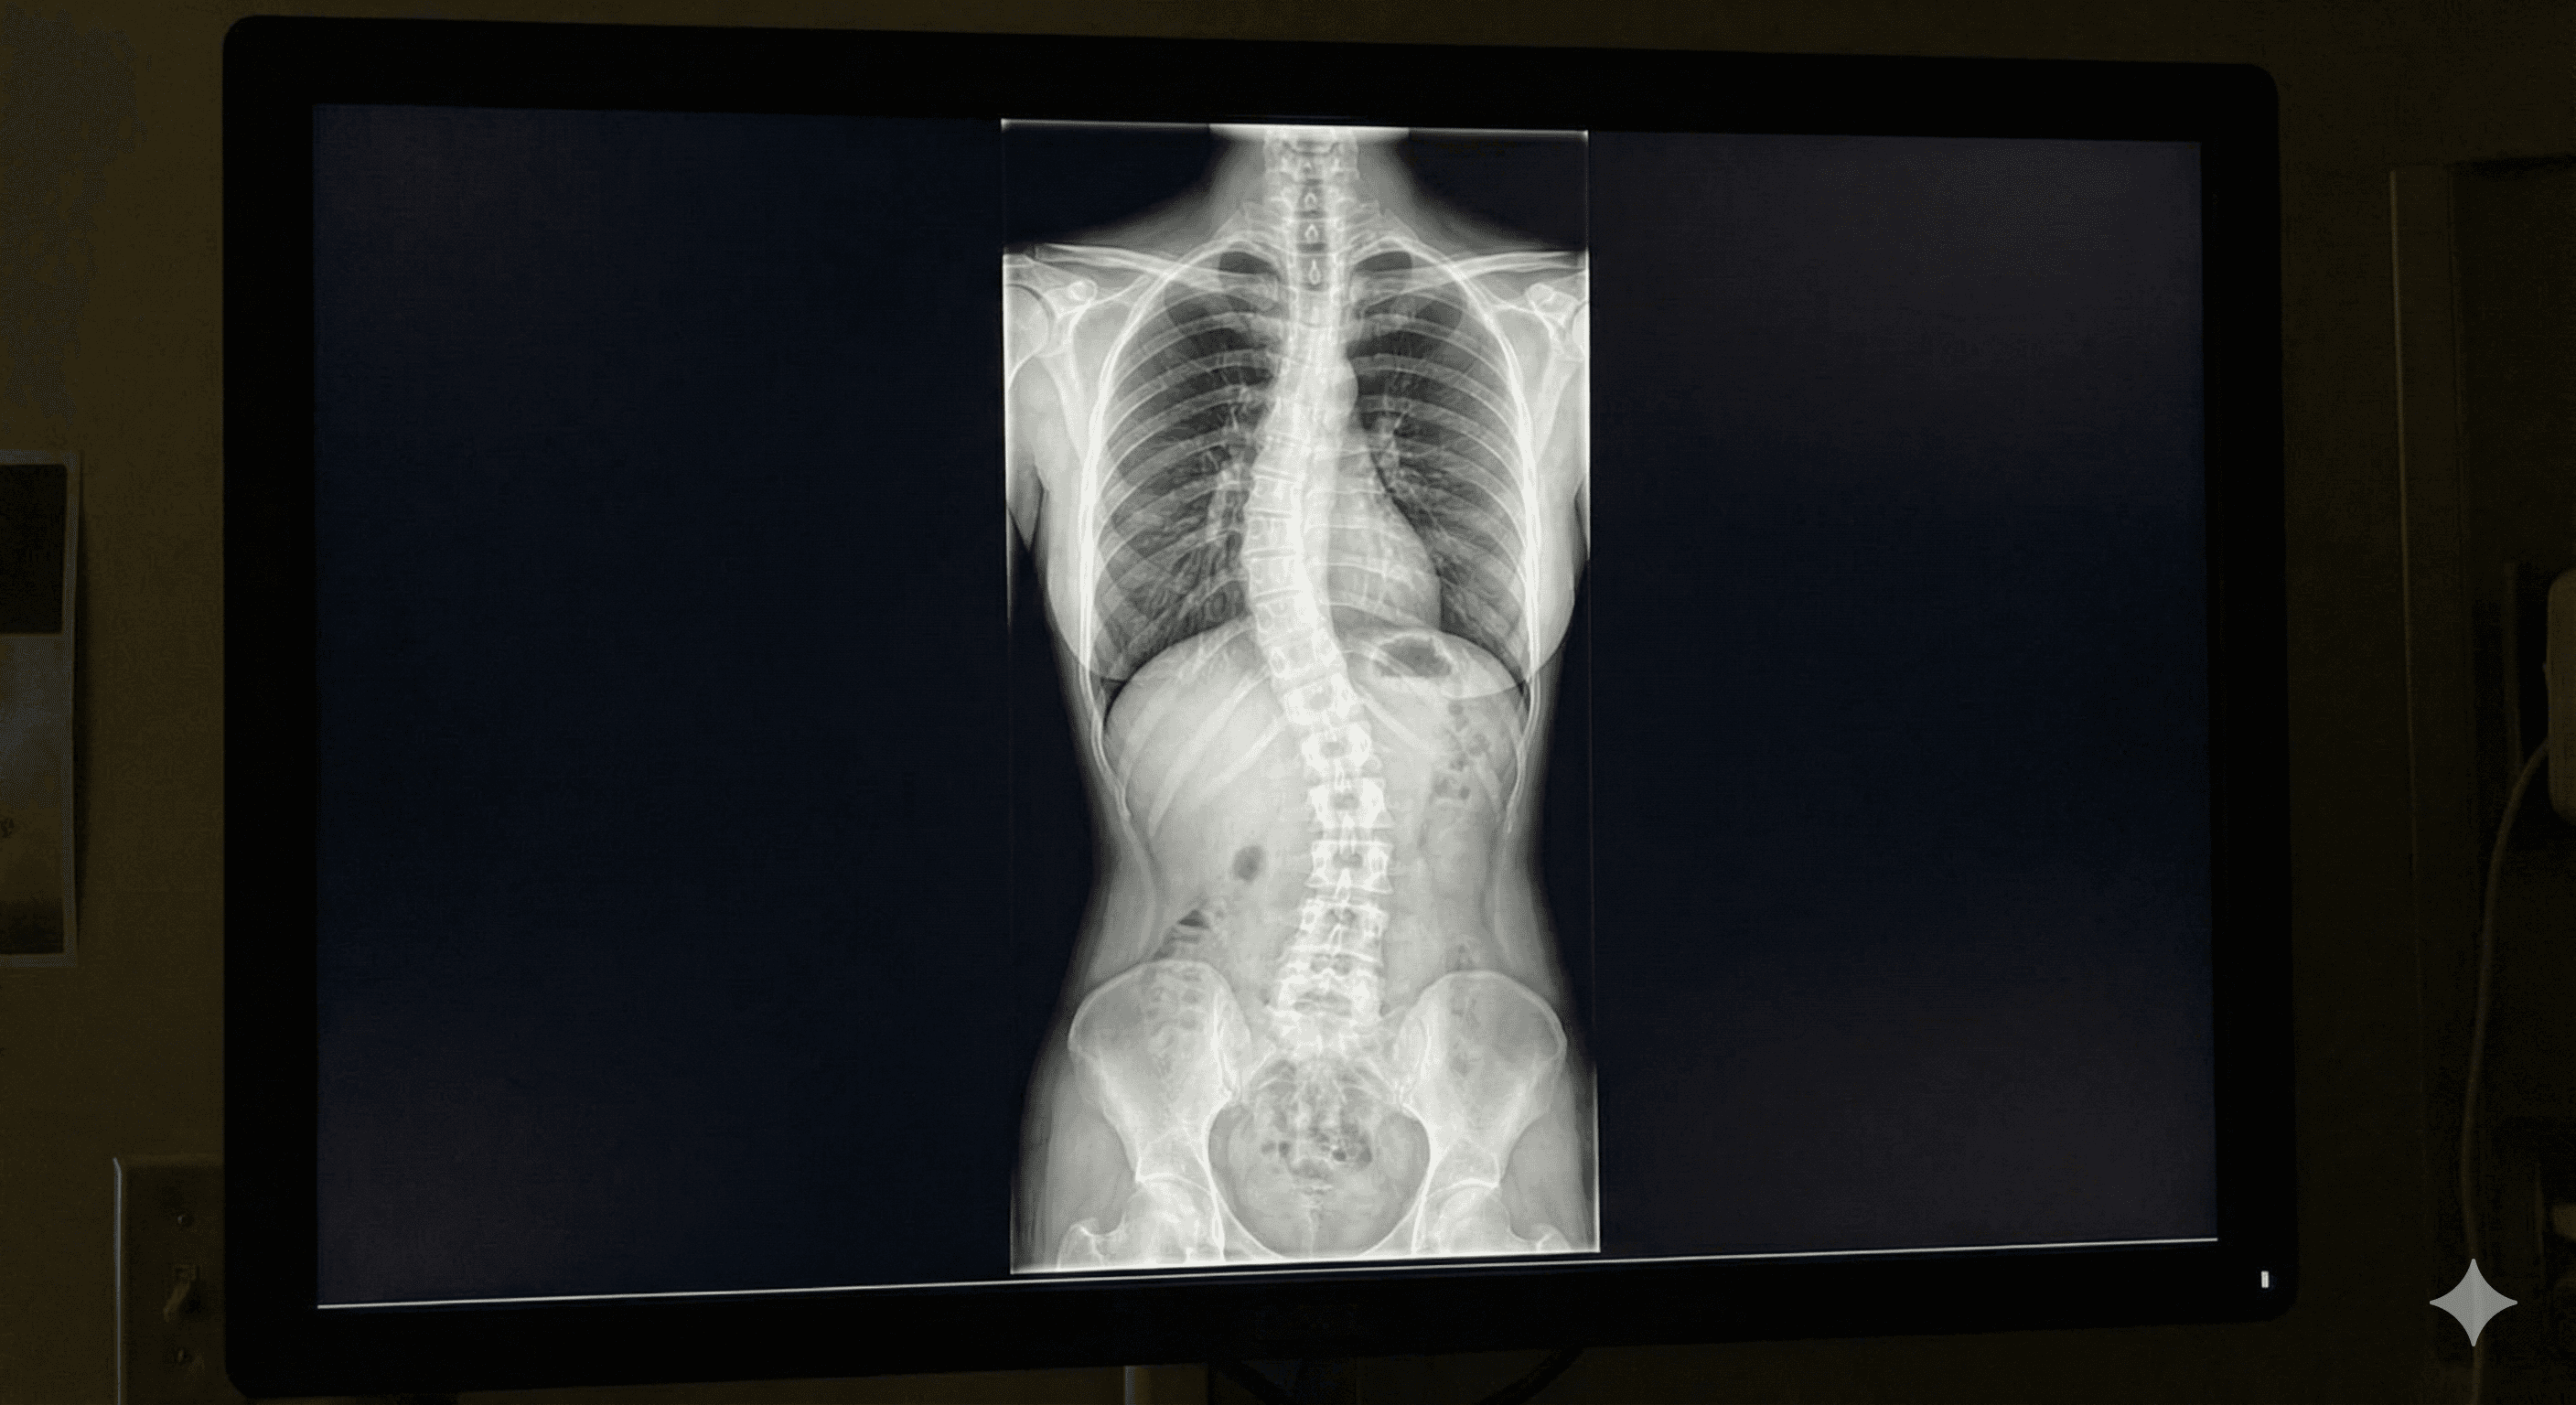

Curvatura anormal de la columna vertebral en forma de 'S' o 'C', que puede causar dolor y problemas posturales.